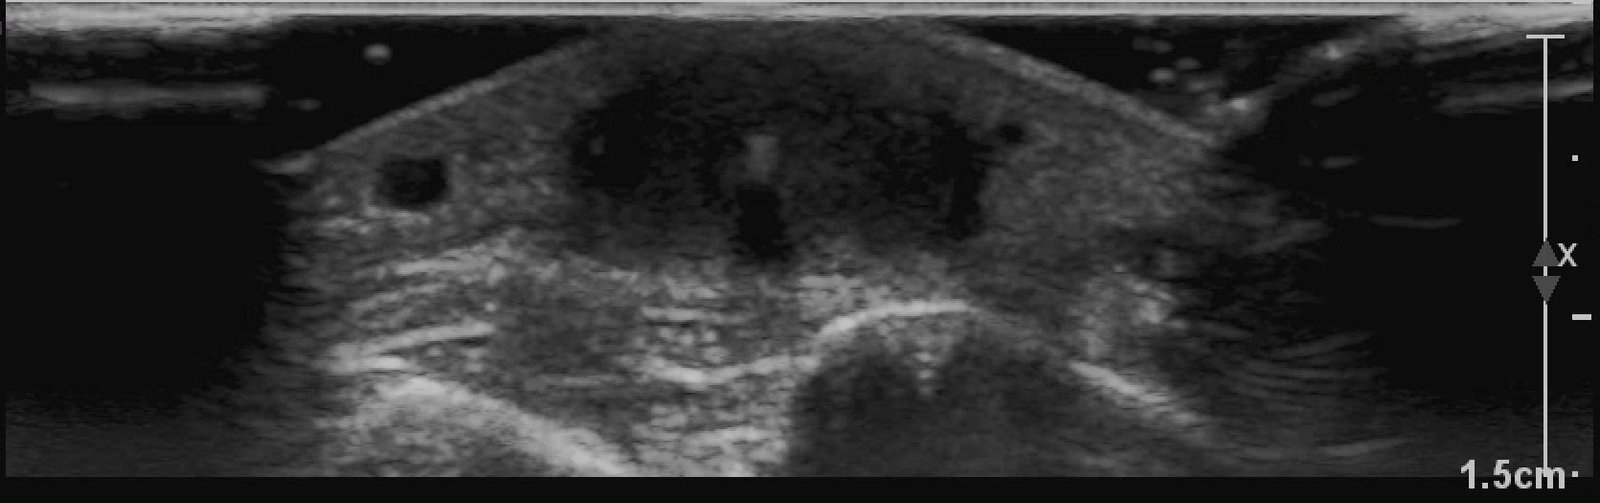

X-rays of the foot were obtained and no radiopaque foreign body was visualized. Due to high clinical suspicion for retained foreign body, a point-of-care ultrasound was performed by applying a high-frequency linear probe at the area of discomfort. In the long axis an ovoid focus of hypoechogenicity (orange outline) is visualized. Within this finding there is a linear focus (yellow line) of increased echogenicity measuring 1 mm in diameter and 1 cm in length. On short axis view, a rectangle focus (green dot) demonstrating shadowing (blue highlight) is seen.